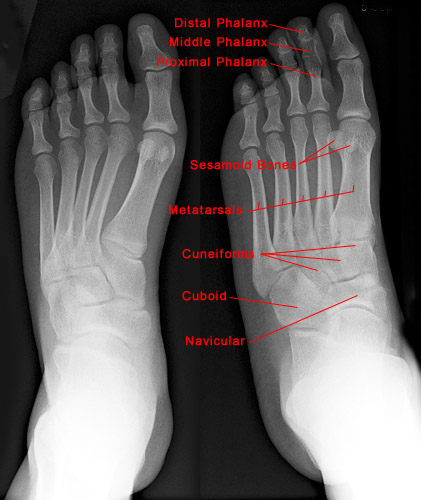

The following images show the normal anatomy of the foot and heel.

• Anatomically, the foot can be divided into three different regions: forefoot, midfoot and hindfoot. The seven tarsal bones of the foot are located within the hindfoot and midfoot, with the hindfoot containing the talus and calcaneus, and the midfoot consisting of the navicular, cuboid, and three cuneiforms. The forefoot contains the metatarsals and phalanges.

• Standard radiographic examination includes AP, lateral and oblique films. Occasionally, a different tangential film may be required for diagnosis.